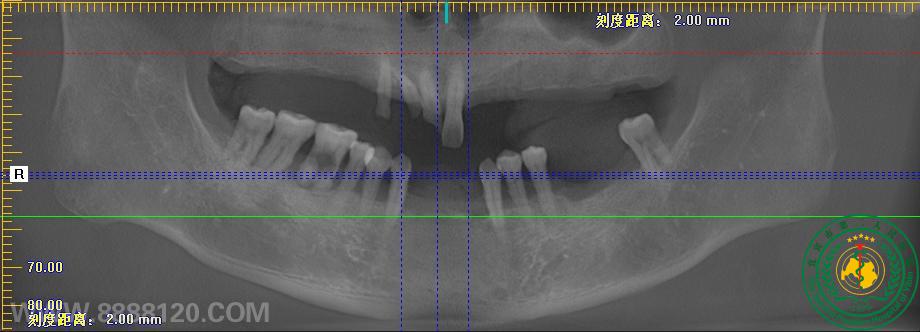

术前,利用软件在电脑模拟种植体植入,制作手术导板。术中,拔除余留牙,上下颌各植入六颗植体。技师通过术前颌位记录等,为患者制作了临时义齿。患者手术当天就能戴牙,恢复咬合关系。术后一周复诊,陈大爷表示假牙用着舒服“缺牙多年,现在终于能畅快的吃东西了!” 陈大爷不禁竖起大拇指。现在,陈大爷只需按时复诊,等待3月后将临时假牙更换成的永久修复体就行了。

术前术后对比